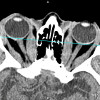

CT orbits.

КТ-орбиты назначают для выявления доброкачественных и злокачественных опухолей, в частности - гемангиом глаза, ретинобластомы. Часто причиной нарушения зрения являются отдаленные метастазы на орбите, распространяющиеся от других органов, пораженных раком. Компьютерная томография орбит показана с механическим повреждением глаз. Сканирование позволяет определить целостность каких структур нарушается, а также установить наличие инородных тел в глазу. В качестве дополнительного диагностического метода его применяют при таких состояниях, как шип, атрофия глазного яблока.

КТ орбиты также используются для выявления воспалительных процессов. Сканирование проводится при подозрении на псевдоопухоль орбиты, при наличии экзофтальма - выпячивание глазного яблока. Показан при гнойных процессах в глазнице - целлюлите, субпериостальном абсцессе. С помощью томографических исследований можно определить степень распространения патологического очага и определить стратегию последующего лечения. Также показанием для КТ-орбит является наличие сильных болей в глазах, быстрое снижение остроты зрения.

По результатам сканирования можно констатировать, что у пациента онкологическое заболевание, определяется тип опухоли, ее точное местоположение и степень распространения на окружающие структуры, а также прогнозируется динамика развития, определяется тактика лечения. Благодаря обнаружению КТ экзофтальма, орбита может определить этиологию заболевания.

КТ-орбита эффективна при диагностике воспалительных и гнойных процессов. На основании полученных данных можно определить частоту поражения близлежащих анатомических структур, чтобы составить план лечения. В случае инородных тел врач может оценить степень повреждения тканей, сделать вывод о необходимости хирургического вмешательства. Контрастный тест позволяет определить уровень кровоснабжения зрительного нерва и глазного яблока. Пациент должен связаться с лечащим врачом, чтобы получить результаты КТ, который поставит точный диагноз и определит следующую стратегию лечения.